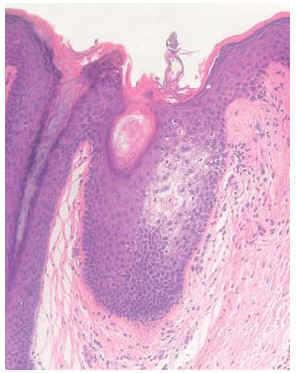

Una mujer de 16 años de edad, sin antecedentes familiares ni personales de interés, que consultó por presentar, desde hacía aproximadamente 3 meses, lesiones papulosas hiperqueratósicas perifoliculares, de 1-2 mm de diámetro, en axilas, formando placas de límites bien definidos, de forma bilateral y simétrica (fig. 1). Estas lesiones eran levemente pruriginosas. Se observaba una disminución del vello axilar. Existían también lesiones similares menos llamativas en areolas mamarias y región púbica. Se realizó biopsia cutánea de las lesiones axilares, que mostró espongiosis en el punto de entrada de la glándula apocrina en el epitelio infundibular, coincidiendo con un tapón córneo suprayacente, y un ligero infiltrado inflamatorio perifolicular (figs. 2 y 3). No presentaba ningún trastorno en las hormonas sexuales ni estaba tomando anticonceptivos orales. Dada la escasa sintomatología, se mantuvo una actitud conservadora y se pautó corticoterapia tópica en caso de cursar con prurito.

Fig. 2.--Piel axilar en la que se observa un foco de espongiosis en el epitelio indundibular. (Hematoxilina-eosina ×20.)

El diagnóstico de este trastorno se basa en la sospecha clínica y se confirma mediante biopsia. Histopatológicamente, los hallazgos típicos consisten en hiperqueratosis ortoqueratósica del conducto excretor apocrino intradérmico, con obstrucción del orificio de salida por tapones ortoqueratósicos, que se acompañan de un infiltrado inflamatorio perifolicular, predominantemente formado por linfocitos. Puede verse dilatación de la glándula apocrina, acantosis epidérmica y espongiosis en la pared del infundíbulo folicular. Este último hallazgo se ha considerado como específico en el diagnóstico5,6. Se ha propuesto la realización de cortes transversos seriados de las piezas de biopsia para asegurar el diagnóstico5, ya que en ocasiones en el examen anatomopatológico convencional con cortes verticales pueden no encontrarse los hallazgos característicos de este trastorno.